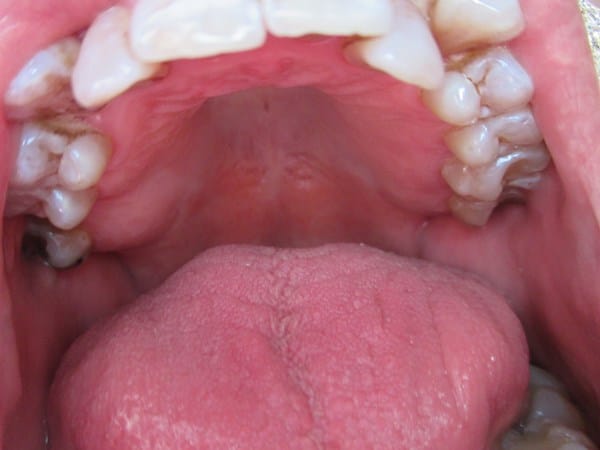

En mi clínica dental un dentista me ha recomendado, a parte de una limpieza, reconstruir (empastar) las piezas 34 y 35, cuando otro dentista me ha dicho que no es necesario la reconstrucción, sobre todo por que me limpio tres veces al día la boca, dentrifico, hilo dental y colutorio de 100% flúor, además no tengo molestias, adjunto fotos para valorar. Una de la parte superior y otro foto de las piezas 34 y 35.